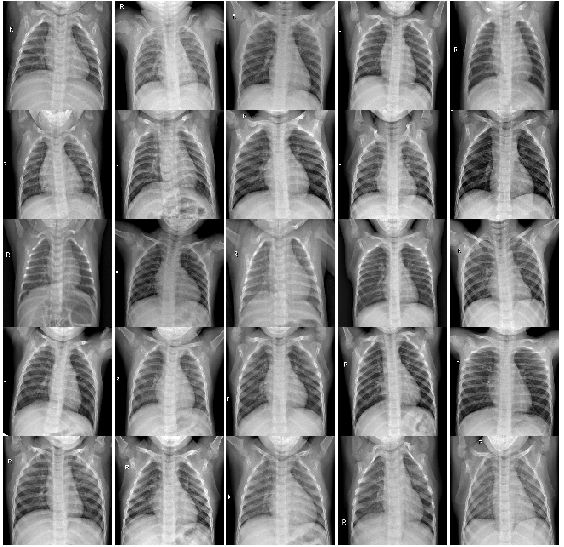

2.2.1 没有肺炎的20个病例的CT图片:

multipleImages = glob('chest_xray/train/NORMAL/**')

i_ = 0

plt.rcParams['figure.figsize'] = (10.0, 10.0)

plt.subplots_adjust(wspace=0, hspace=0)

for l in multipleImages[:25]:

im = cv2.imread(l)

im = cv2.resize(im, (128, 128))

plt.subplot(5, 5, i_+1) #.set_title(l)

plt.imshow(cv2.cvtColor(im, cv2.COLOR_BGR2RGB)); plt.axis('off')

i_ += 1